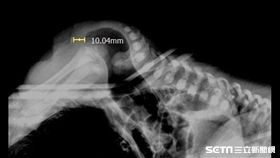

驚!男嬰「天生沒肛門」醫緊急搶救

在婦產科診所出生的黃小弟,出生檢查時被發現無肛門,經...